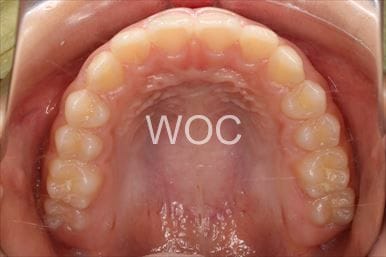

治療前1

治療前2

治療前3

治療前4

治療前5

- 年齢:7歳9ヶ月

- 主訴:スペースがない、デコボコしている

- 診断名:叢生、上顎前突、過蓋咬合

- 装置:可撤式拡大装置、機能的矯正装置

- 期間:4年1ヶ月 ※

- 費用:基本矯正料金:380,000円